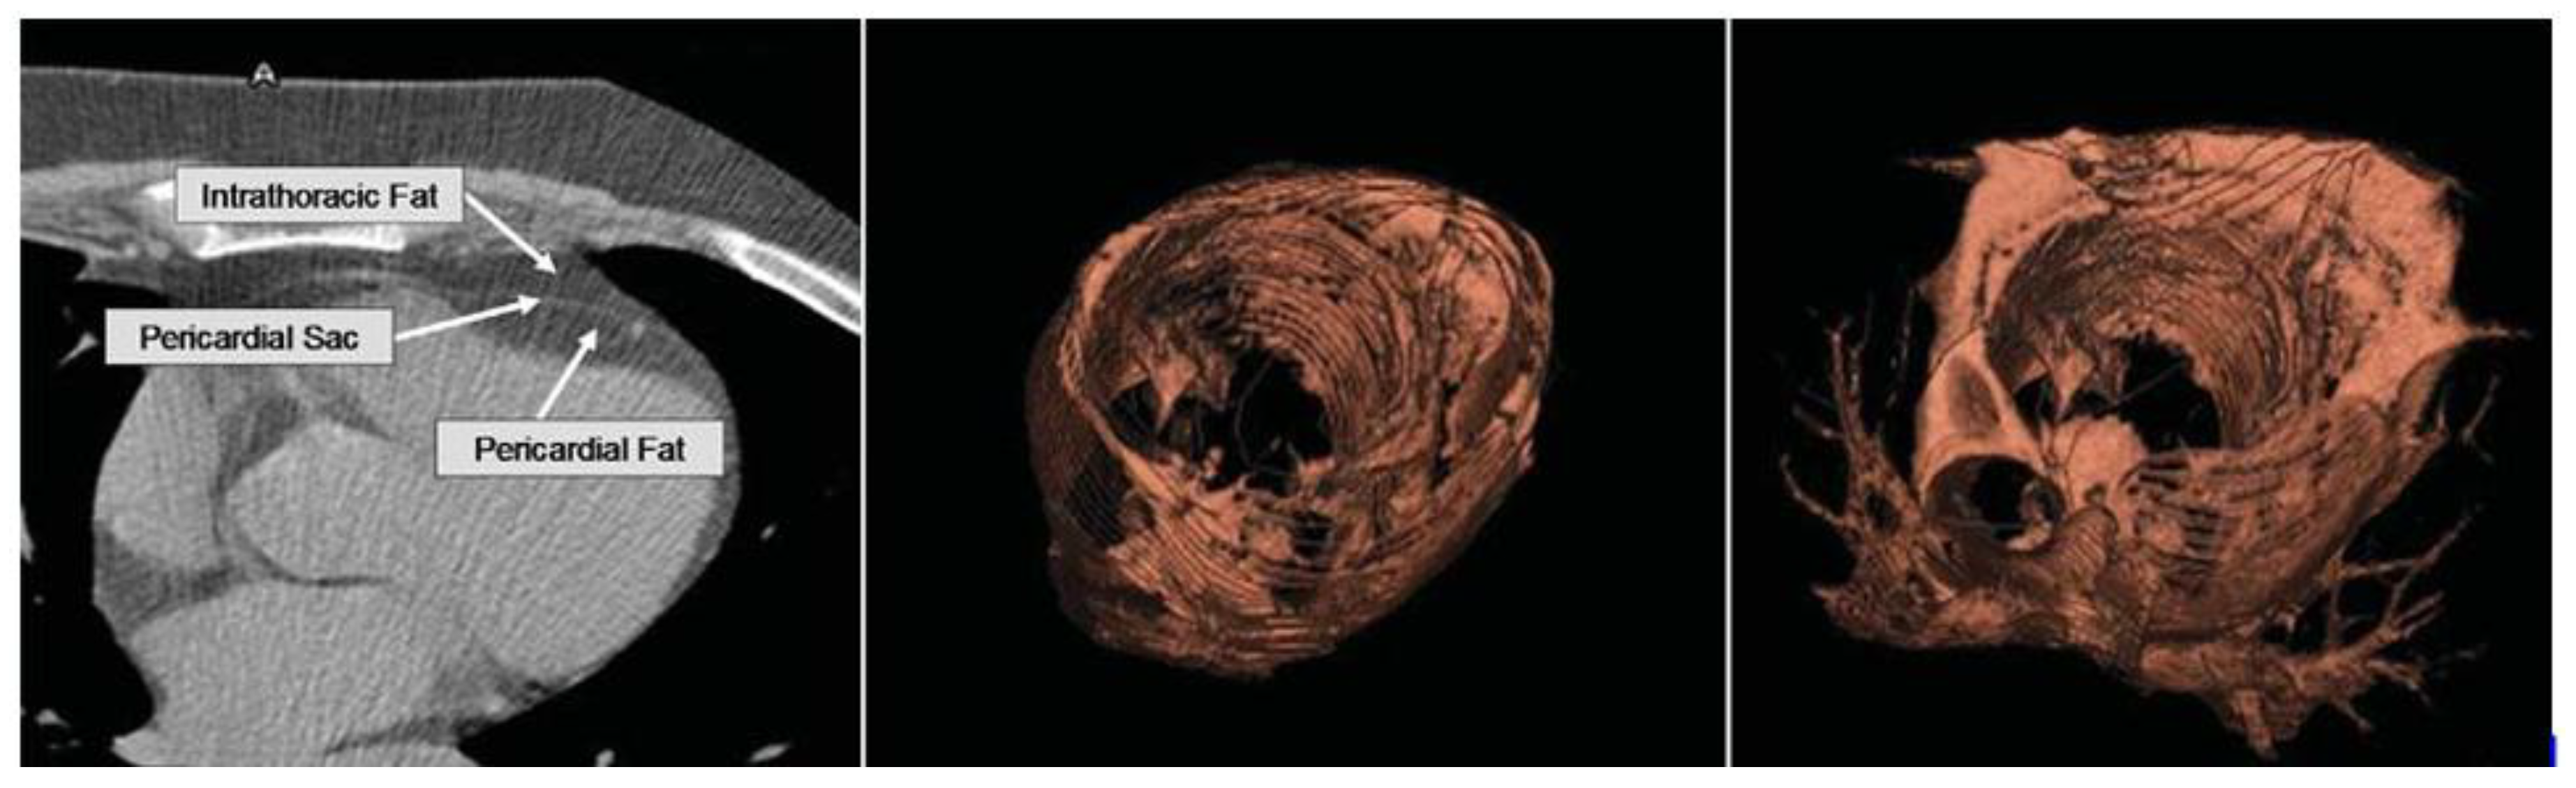

2.1. Epicardial Adipose Tissue

2.2. Pericardial Adipose Tissue

2.3. Paracardial Adipose Tissue